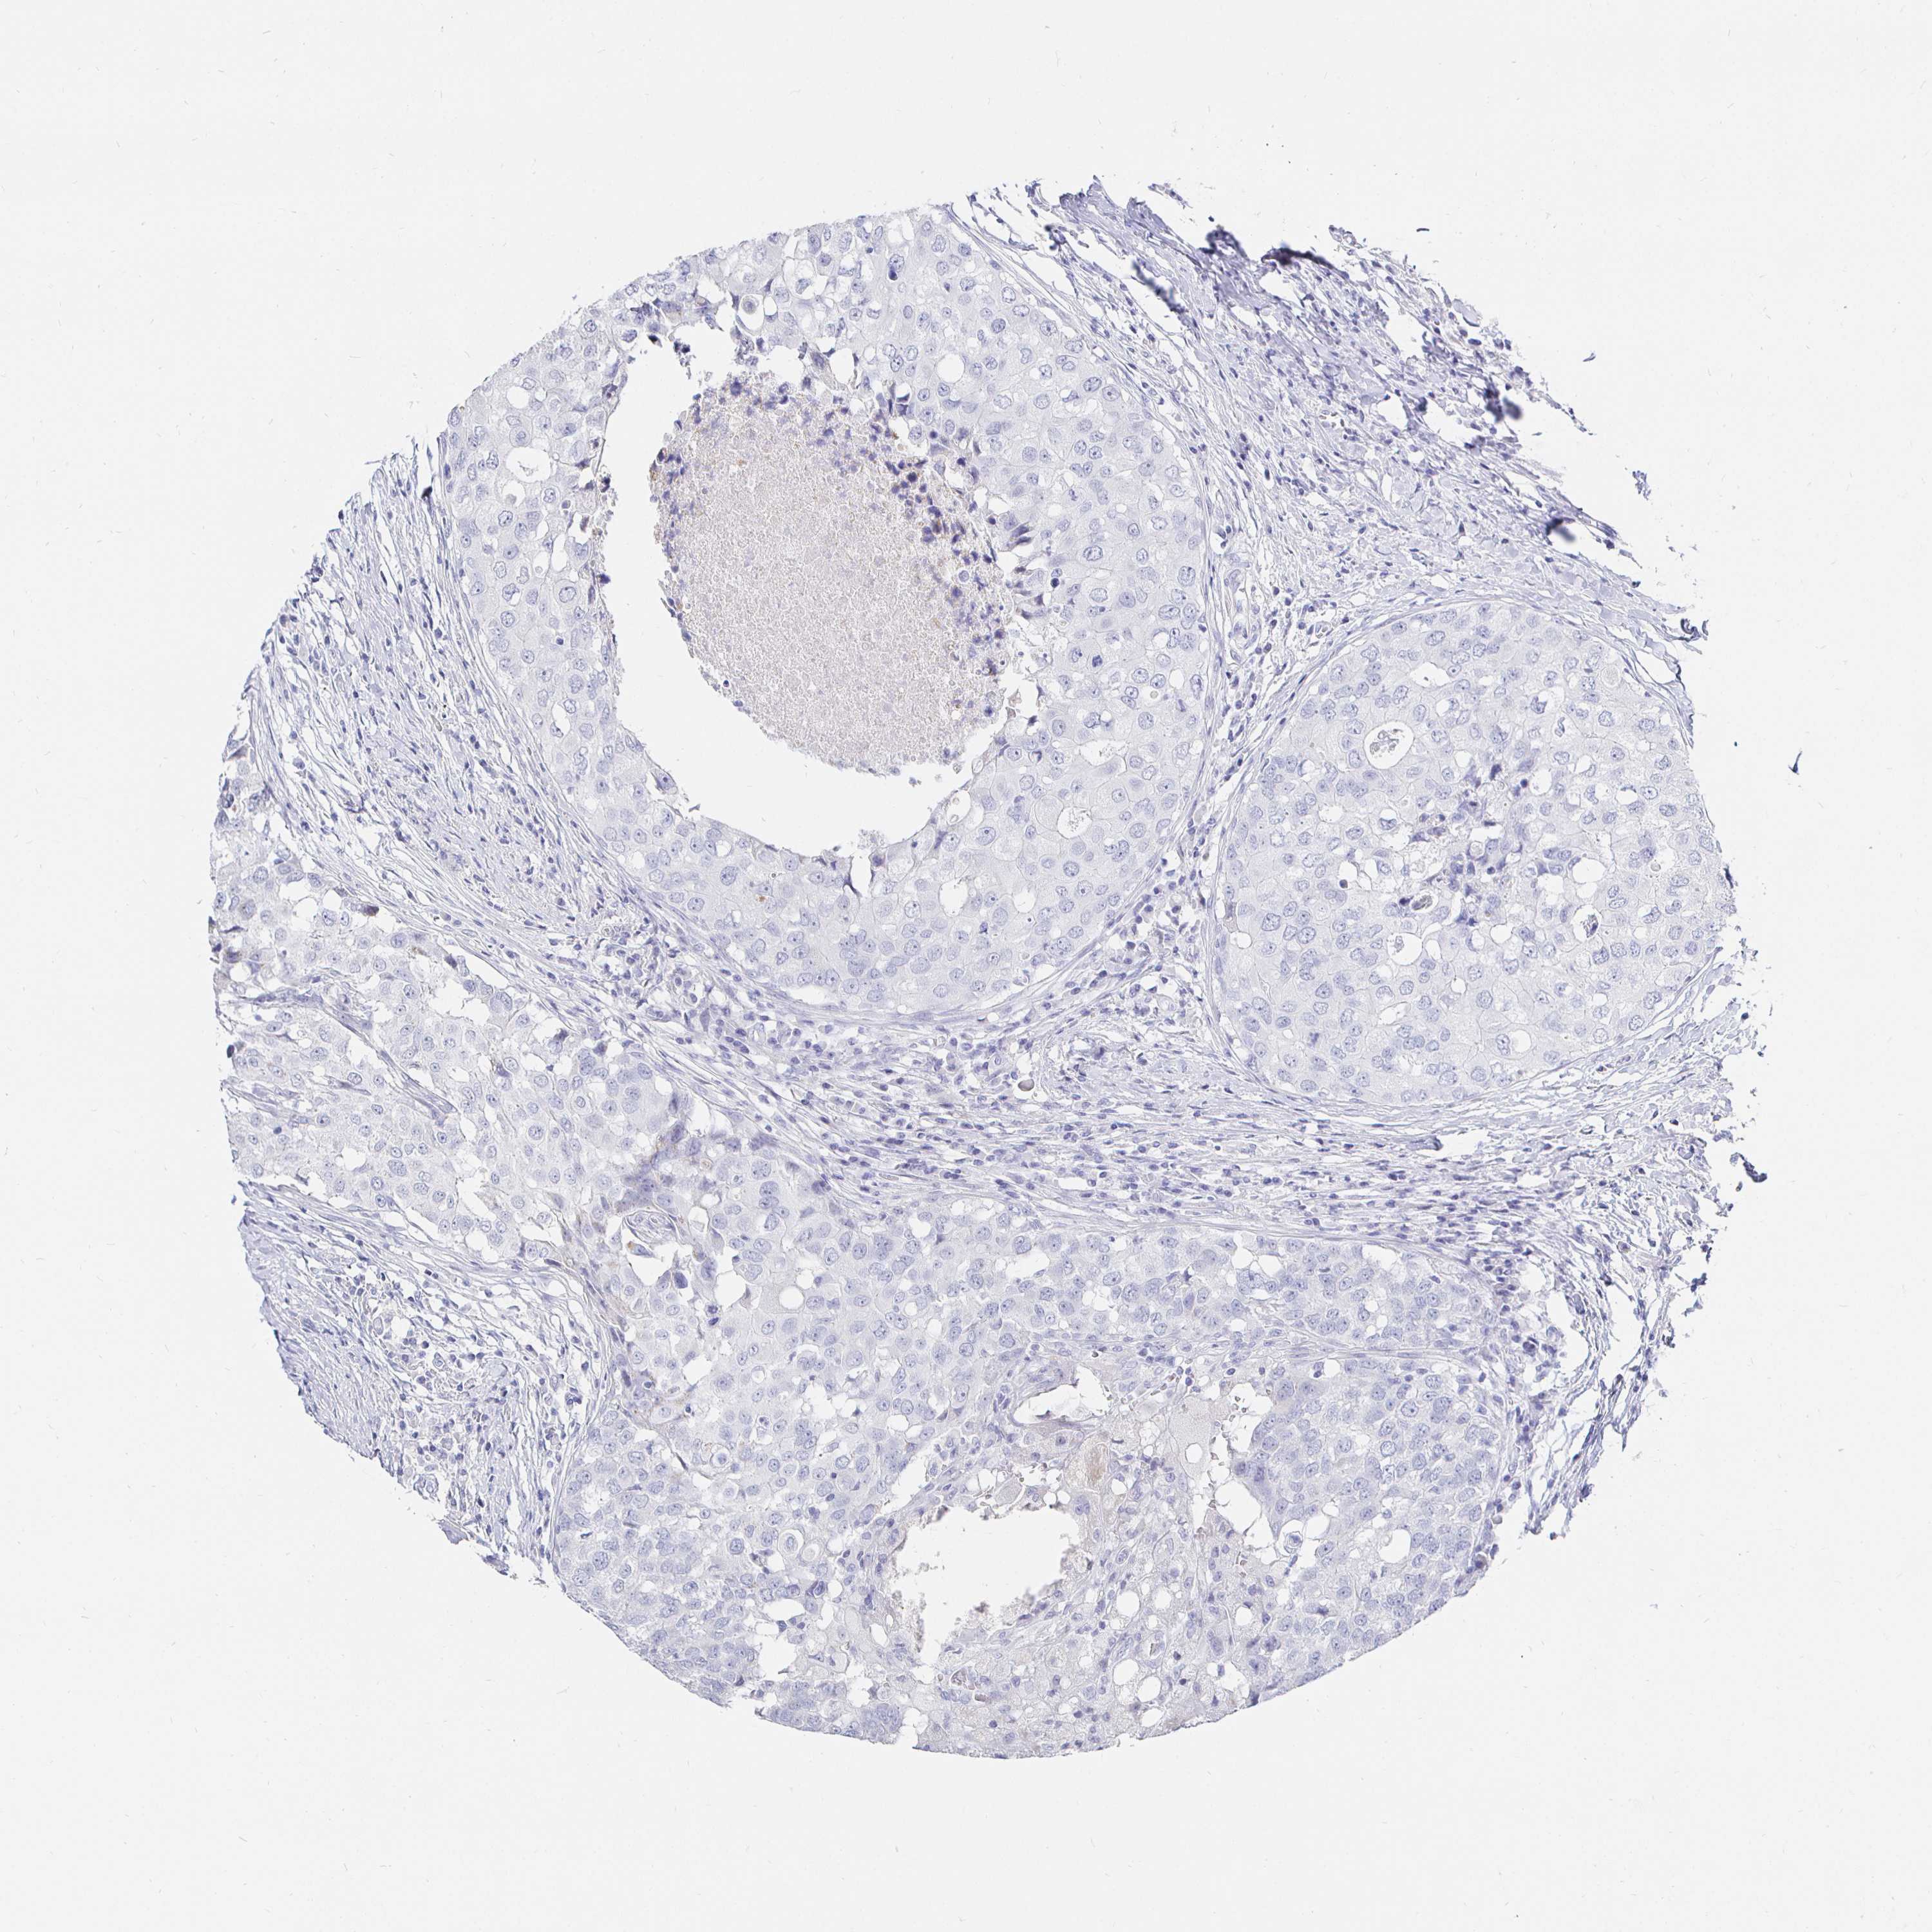

BRCA TCGA BRCA VALIDATION PROTEIN EXPRESSION

Breast cancer

Human cancer

CR2 is potential prognostic, high expression is favorable in Breast Invasive Carcinoma (TCGA)